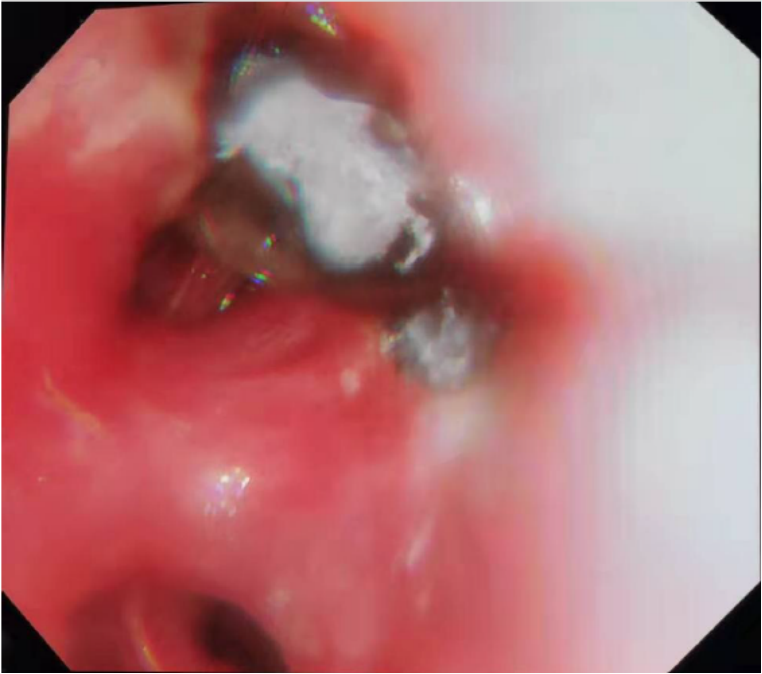

2021125日再次复查气管镜:左肺上叶开口侧壁膜可见片状灰黑色坏死物附着,表面见白色霉菌斑15,余各叶段膜充血,管腔内无明显分泌物。

BALF真菌涂片:可见真菌菌丝;BALF GM阴性;真菌培养结果未归。

图片

15  复查气管镜(2021-01-25,术后第26天)

由此,找到干咳元凶——气道真菌感染!